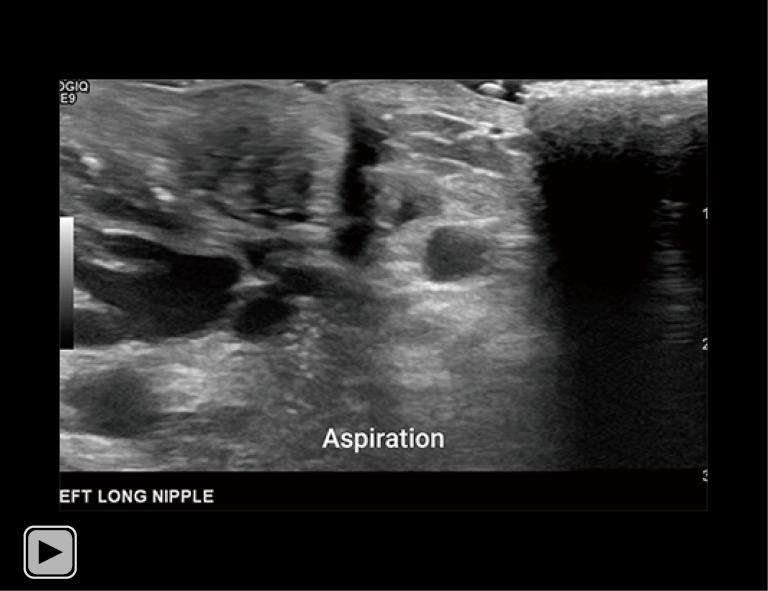

A 34-year-old lactating female presented with a 3-month history of worsening left breast and nipple pain radiating to the left upper outer quadrant, not relieved with conservative therapies. The physical exam revealed a small indentation and a small palpable nodule of the left nipple. There was no associated erythema or redness. Targeted ultrasound and subareolar magnification views revealed findings most consistent with a probably benign inspissated clogged milk duct. Given the patient's history, inability to express milk from the left breast, and plan to lactate for another year, ultrasound-guided aspiration was desired. Post-aspiration images demonstrated complete resolution of the nipple mass. Pathology revealed blood and proteinaceous material, in keeping with the diagnosis of inspissated clogged milk duct. Following the procedure, the patient's symptoms resolved completely.

一名34岁的哺乳期女性,左乳房和乳头疼痛加剧3个月,疼痛放射至左乳房外上象限,保守治疗未能缓解。体格检查发现左乳头有一个小凹陷和一个可触及的小结节。无相关红斑或发红。针对性超声检查和乳晕下放大视图显示的结果最符合可能为良性的浓缩性乳腺管堵塞。鉴于患者的病史、左乳房无法挤出乳汁以及计划再哺乳一年,希望进行超声引导下抽吸。抽吸后的图像显示乳头肿块完全消失。病理检查显示为血液和蛋白质物质,符合浓缩性乳腺管堵塞的诊断。手术后,患者症状完全缓解。